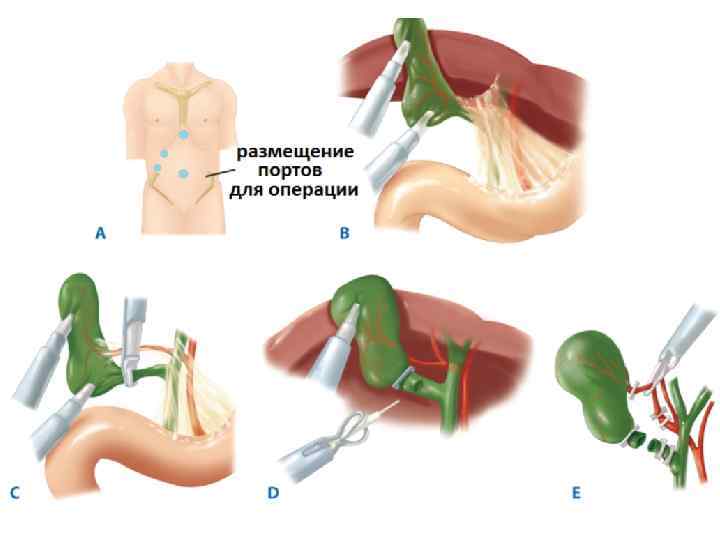

Лапароскопиялық холецистоэктомия Көрсеткіші: жедел холецистит (егер операцияны ауыру басталғаннан 48 сағат аралығында жасаса). Қарсы көрсеткіштері: айқын жүрек-өкпелік жеткіліксіздік; емге көнбейтін қан ұю бұзылыстары; жайылған перитонит; іштің алдыңғы қабырғасының қабыну өзгерістері; жүктілік (II-III триместр); семіздік III-IV степень; ауыру басталғаннан 48 сағаттан кейін; механикалық сарғаю; іш қуысының жоғарғы этажында бұрын болған операциялар кезінде.